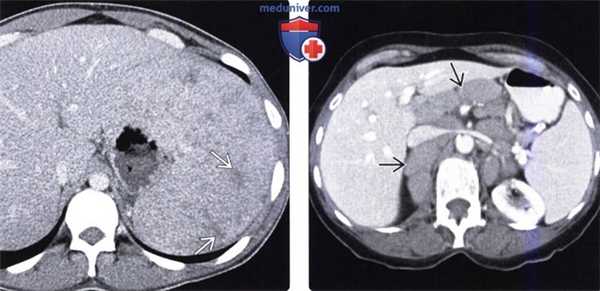

б) Вопросы лучевой диагностики. Селезенка имеет уникальную тканевую структуру и состоит из красной и белой пульпы, что обусловливает ее характерный вид при лучевых исследованиях. Белая пульпа образована лимфоидной тканью, а красная - сосудами и селезеночными тяжами (скоплениями клеток, разделенными синусоидами). В связи с большим количеством кровеносных сосудов красная пульпа быстро накапливает контраст, из-за чего структура селезенки становится неоднородной в артериальную фазу КТ- либо МР-исследования. Эту особенность можно ошибочно принять за патологические изменения, однако данный феномен не определяется при исследованиях без контрастного усиления либо в отсроченную фазу.

(Слева) На аксиальной КТ в артериальную фазу контрастного усиления определяется выраженная неоднородность структуры селезенки в результате быстрого накопления контраста в сосудистых синусоидах (красной пульпе), что не должно ошибочно приниматься за патологический процесс.

(Слева) На аксиальной КТ с контрастом в венозную фазу селезенка выглядит однородной. (Слева) На аксиальной Т1 ВИ МР томограмме (А) визуализируется неизмененная селезенка, несколько гипоинтенсивная по отношению к паренхиме печени. На Т2 ВИ МР томограмме (В) сигнал от селезенки в норме слегка более интенсивен, чем от печени.

(Справа) На аксиальной КТ с контрастным усилением визуализируется «объемное образование» в хвосте поджелудочной железы, имеющее одинаковую плотность с селезенкой (добавочная селезенка), которое можно ошибочно принять за первичную (например, нейроэндокринную) опухоль поджелудочной железы. Медиальная поверхность селезенки, а также аксиальные срезы на трех различных уровнях. Селезенка может иметь различный размер и форму даже у одного и того же человека в зависимости от гидратации и питания. С медиальной стороны селезенки часто имеется участок, выбухающий в промежуток между желудком и почкой. Селезеночная артерия и вена, располагающиеся в селезеночно-почечной связке, проходят параллельно телу поджелудочной железы. Хвост поджелудочной железы также проникает в ворота селезенки через селезеночно-почечную связку. В желудочно-селезеночной связке находятся короткие артерии желудка и левая желудочно-сальниковая артерия, кровоснабжающие желудок и верхнюю часть селезенки.